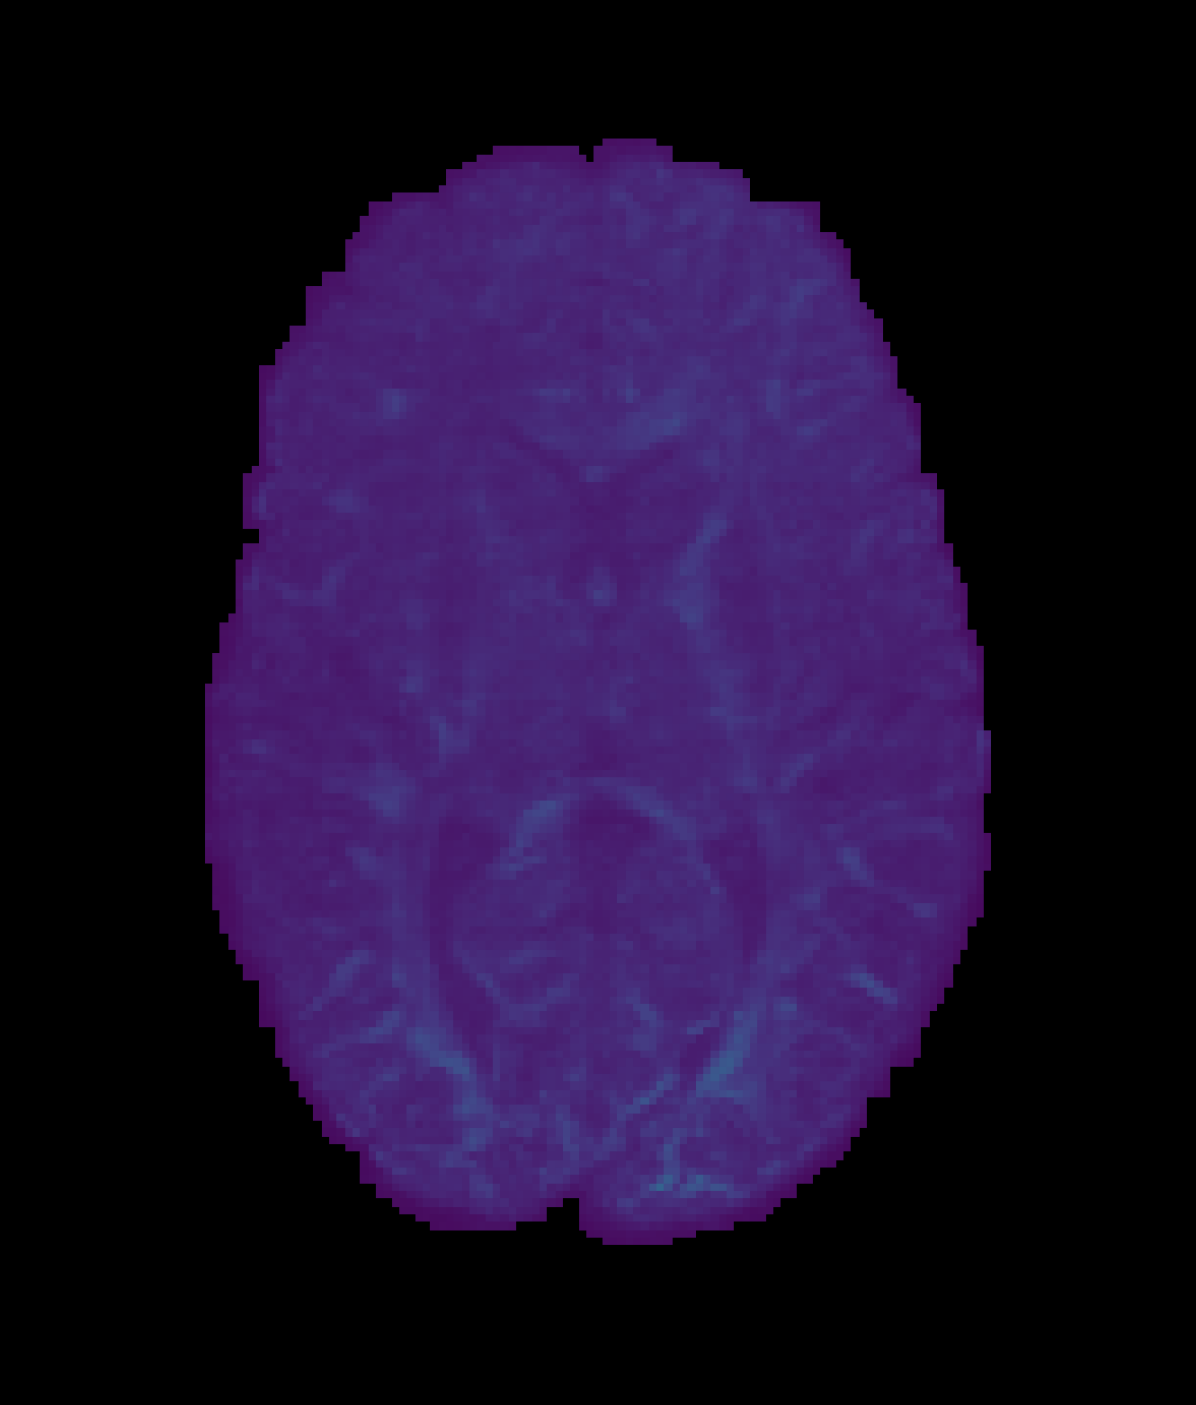

In this experiment, the PCCNN models perform competitively, yielding the lowest error in fisosubscript𝑓isof_{\mathrm{iso}} and fintrasubscript𝑓intraf_{\mathrm{intra}} across all three sub-sampling rates. The relative error in OD across different models mirrors that of the FOD ACC found in Table 4, suggesting that the trained models are able to infer data that generalise across different downstream analyses. The worst performing model across all sub-sampling schemes was the SR-q-DL model, as is demonstrated qualitatively by Figure 4. Whilst this model could benefit from the more constrained task of inferring NODDI data directly, the lack of geometric prior information, such as b-vector coordinates, suggests that these additions within the PCCNN models were important to its relatively high performance in this task.

Refer to caption

(a) High Resolution

(b) SR-q-DL

(c) RCNN

Refer to captionRefer to caption

(d) PCCNN-Bv

Figure 4: Axial slice of orientation dispersion index (OD) within one subject across different models. Models use single-shell data (b=1000s/mm2𝑏1000ssuperscriptmm2b=1000\mathrm{s/mm^{2}}) with angular dimension size qin=10subscript𝑞in10q_{\mathrm{in}}=10 as input, and produce 808080 b=1000s/mm2𝑏1000ssuperscriptmm2b=1000\mathrm{s/mm^{2}}, 909090 b=2000s/mm2𝑏2000ssuperscriptmm2b=2000\mathrm{s/mm^{2}}, and 909090 b=3000s/mm2𝑏3000ssuperscriptmm2b=3000\mathrm{s/mm^{2}} inferred volumes.